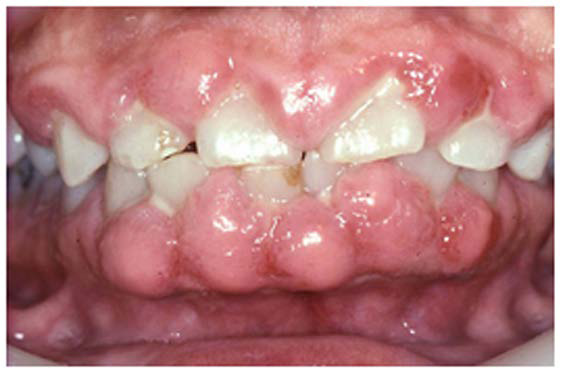

Gingival overgrowth may be associated with the administration of calcium-channel blocking agents, phenytoin, and cyclosporine.13-16 The mechanisms responsible are unclear, but they appear to be related to altered calcium metabolism and concomitant poor oral hygiene-related inflammation.13While the enlarged tissue is usually firm and painless, it may interfere with mastication; and, with significant inflammation, the patient may report pain and gingival bleeding (Figure 9 and Figure 10).

Fig 10. Cyclosporine-induced Gingival Overgrowth.

Figure 10